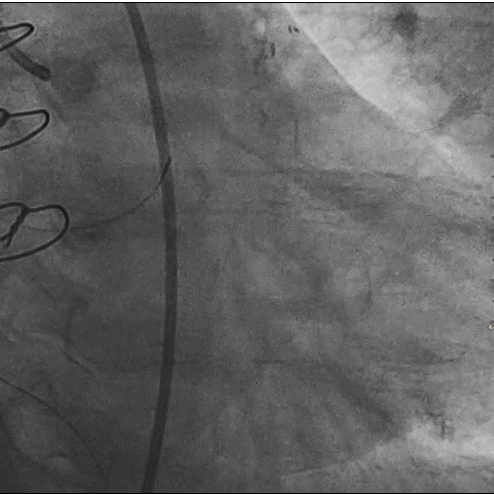

造影图:

LM呈鸟嘴样狭窄,

LAD为迂曲弥漫性病变,中段最重处狭窄80%,曾搭桥已闭塞。RCA曾植入支架,中段支架内反复再狭窄。